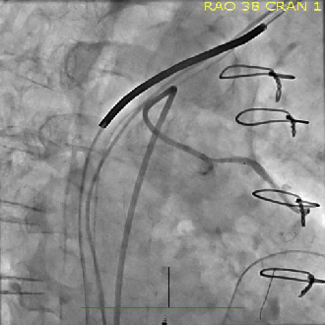

Bibhav Poudel, BS; Atharva Dhole, MD; Grace Pyon, BS; Maria Litzendorf, MD; Scott Brannan, MD; Nikhil Patel, MD

The authors present the case of a diabetic patient with a right plantar hallux ulceration, CTO of arteries supplying the right hallux on angiogram despite benign non-invasive testing, and the effects of revascularization in the region.